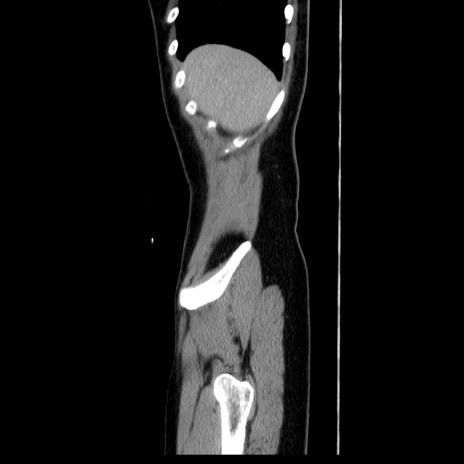

症例39(矢状断像)

【症例】40歳代女性

【主訴】上下腹部痛

【現病歴】2日目から下腹部痛あり。夜間は痛みで眠れなかった。昨日より上腹部痛と下痢が出現。臥位で痛みは軽快したため、休んでいた。本日になって臥位でも立位でも痛みが強くなってきたため救急要請。

【既往歴】子宮内膜症

【身体所見】部:平坦・軟、左上下腹部に圧痛あり、反跳痛あり。

【データ】WBC 21800、CRP 26.78

CT